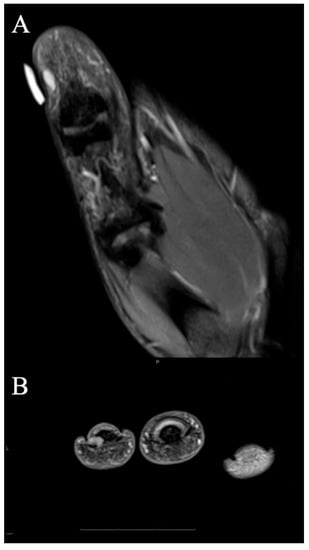

2.2.2. Imaging Appearance

- Wang, C.; Song, R.-R.; Kuang, P.-D.; Wang, L.-H.; Zhang, M.-M. Giant cell tumor of the tendon sheath: Magnetic resonance imaging findings in 38 patients. Oncol. Lett. 2017, 13, 4459–4462. [Google Scholar] [CrossRef]